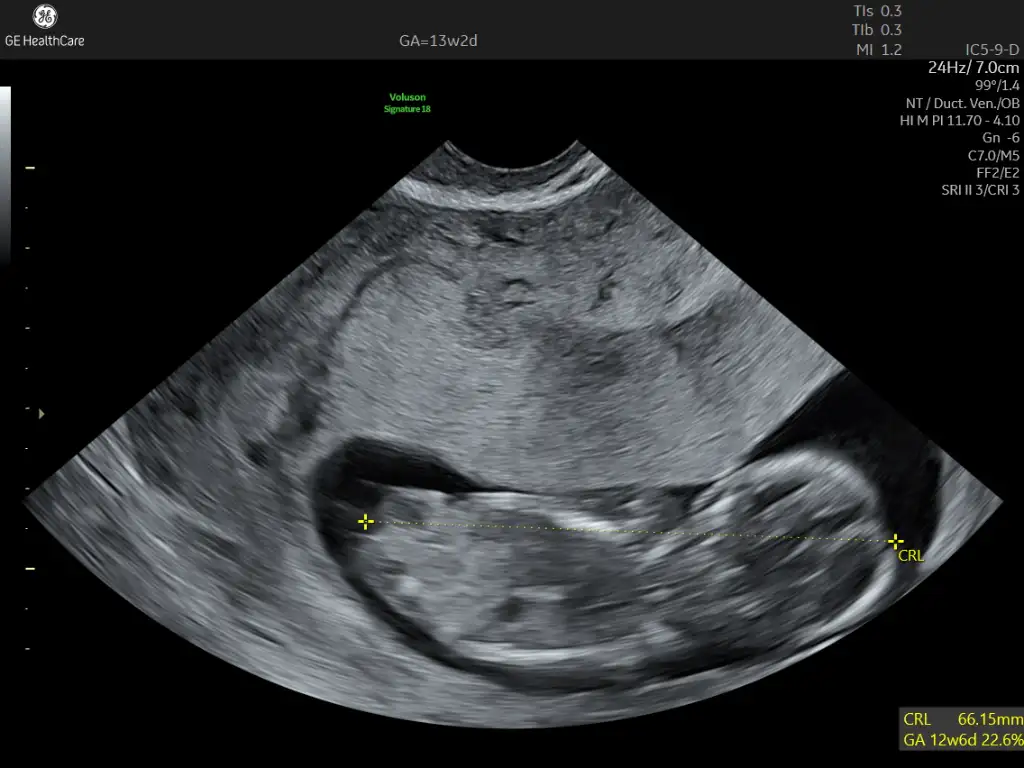

Nub teorisi cinsiyet

Sizce cinsiyeti nedir ? Tahmin alabilir miyim 🤭

Benimkini de yorumlar mısınız 11 haftalık 😊